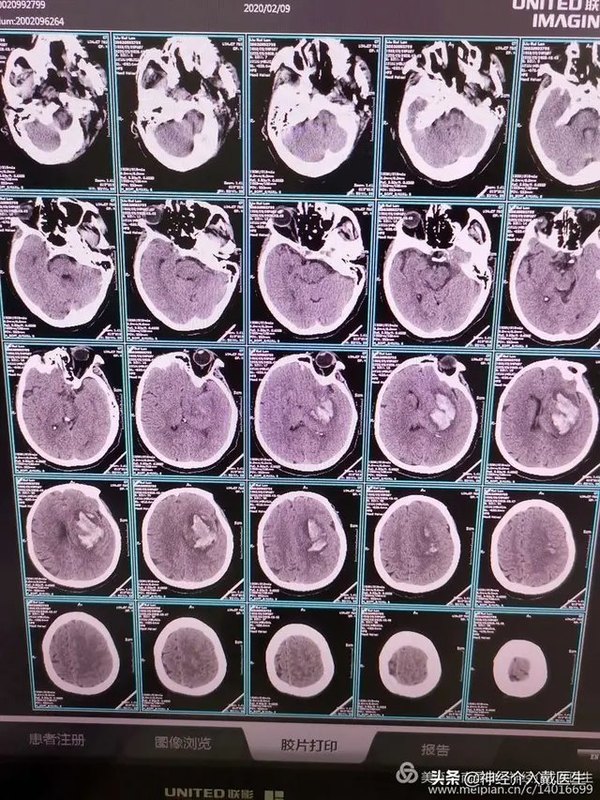

某嘗說知是行的主意,行是知的功夫;知是行之始,行是知之成。若會得時,只說一個知已自有行在,只說一個行已自有知在。古人所以既說一個知又說一個行者,只為世間有一種人,懵懵懂懂的任意去做,全不解思維省察,也只是個冥行妄作,所以必說個知,方才行得是;又有一種人,茫茫蕩蕩懸空去思索,全不肯著實躬行,也只是個揣摸影響,所以必說一個行,方才知得真。 某今說個知行合一,正是對病的藥。又不是某鑿空杜撰,知行本體原是如此。 —— 王陽明《傳習錄》 做為醫(yī)者,也必須知行合一。在實踐中不斷思考,以更小的損傷,達到更好的效果,并努力實現(xiàn)! 女,63歲,突然神志不清2小時于 2月9日早晨7點半急診入院,既往高血壓十年,偶爾服藥治療。入院查:脈搏70次/分,血壓200/95mmHg,昏迷,GCS計8分,雙側(cè)瞳孔直徑3mm,對光反射遲鈍,右側(cè)肢體偏癱,病理征陽性。 頭部CT顯示左側(cè)基底節(jié)區(qū)腦出血,血腫量接近60ml,血腫形態(tài)不是很規(guī)則,提示仍然繼續(xù)出血可能。 顱內(nèi)出血量大,超過30ml,神志昏迷,CT腦室中線受壓明顯,有明確手術(shù)指征,高血壓腦出血手術(shù)方式有大骨瓣開顱血腫清除術(shù),小骨窗開顱血腫清除術(shù),鎖孔開顱血腫清除術(shù),神經(jīng)內(nèi)徑下血腫清除術(shù),顱骨鉆孔軟通道血腫引流術(shù)等。我們綜合評估,決定采用鎖孔開顱血腫清除術(shù)。左側(cè)顳部直切口,長約8cm。 切開頭皮,撐開器撐開,取下骨瓣。 骨瓣直徑3cm,開始以為有3.5cm,后來用尺量了一下,5ml注射器的一大格沒有1cm。 術(shù)后傷口,下次使用美容縫合。 手術(shù)很順利,術(shù)中出血也不多,術(shù)中術(shù)后生命體征平穩(wěn),復查CT腦出血基本清除,達到手術(shù)目的。 三維CT顯示骨瓣情況。 第二天上午查看病人,沒有使用降壓藥的情況下,血壓124/80mmHg,神志基本清楚,可以遵命握手。 鎖孔神經(jīng)外科指通過位置合適的小骨窗(直徑2-3cm)進行顯微外科或內(nèi)鏡輔助顯微神經(jīng)外科手術(shù)。用小骨窗顯露顱內(nèi)深部大的病變。 鎖孔外科不僅指通過位置合適的小骨窗(直徑2-3cm)進行顯微外科或內(nèi)鏡輔助顯微外科省手術(shù),而且鎖孔外科強調(diào)術(shù)前術(shù)后精心的診斷和處理,個體化地設(shè)計手術(shù)方案,應(yīng)用準確、便捷的手術(shù)入路去接近和處理病變,盡量減少對顱內(nèi)結(jié)構(gòu)的暴露和損傷,以期最低也達到與標準顯微外科手術(shù)一樣的療效。因此,要求外科醫(yī)生有扎實的顯微外科技術(shù),術(shù)前精心制定手術(shù)方案是手術(shù)成功的關(guān)鍵,包括復習病史、體檢、神經(jīng)影像學資料和實驗室檢查等,制定個體化的手術(shù)方法和手術(shù)入路,后者包括患者體位、皮膚切口、骨窗位置、硬腦膜切口、顱內(nèi)蛛網(wǎng)膜下腔入路等。 該手術(shù)只是單純清除顱內(nèi)血腫,沒有顯微鏡的情況下也是可以完成的。 鎖孔開顱手術(shù),可以減少出血,減少對神經(jīng)組織的損傷,減少耗材的使用,減少病人的費用,但是一但術(shù)中大出血,也是麻煩的事情,所以術(shù)前需要充分評估,最主要的是對自己要有信心!